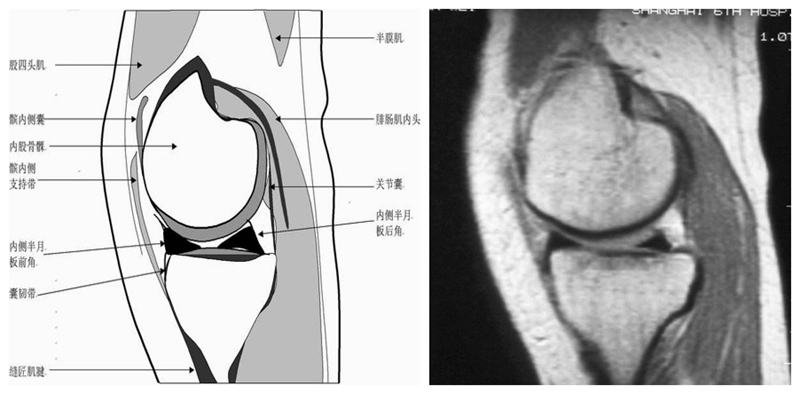

膝关节矢状面正常解剖MRI表现

可整段显像髌韧带、前后交叉、外侧韧副带结构,侧重的股胫软骨中部和半月板前后角,通常是诊断半月板撕裂或变性最为关键的断面。

矢状位解剖第三层

矢状位解剖第四层